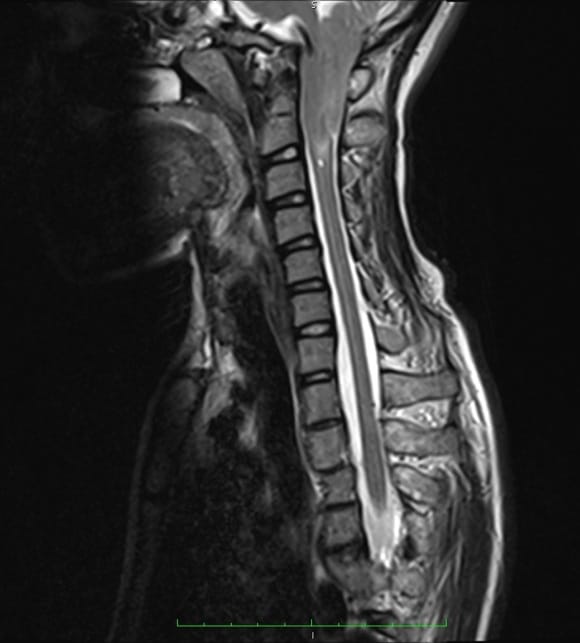

Аномалия Арнольда-Киари: MRI снимки